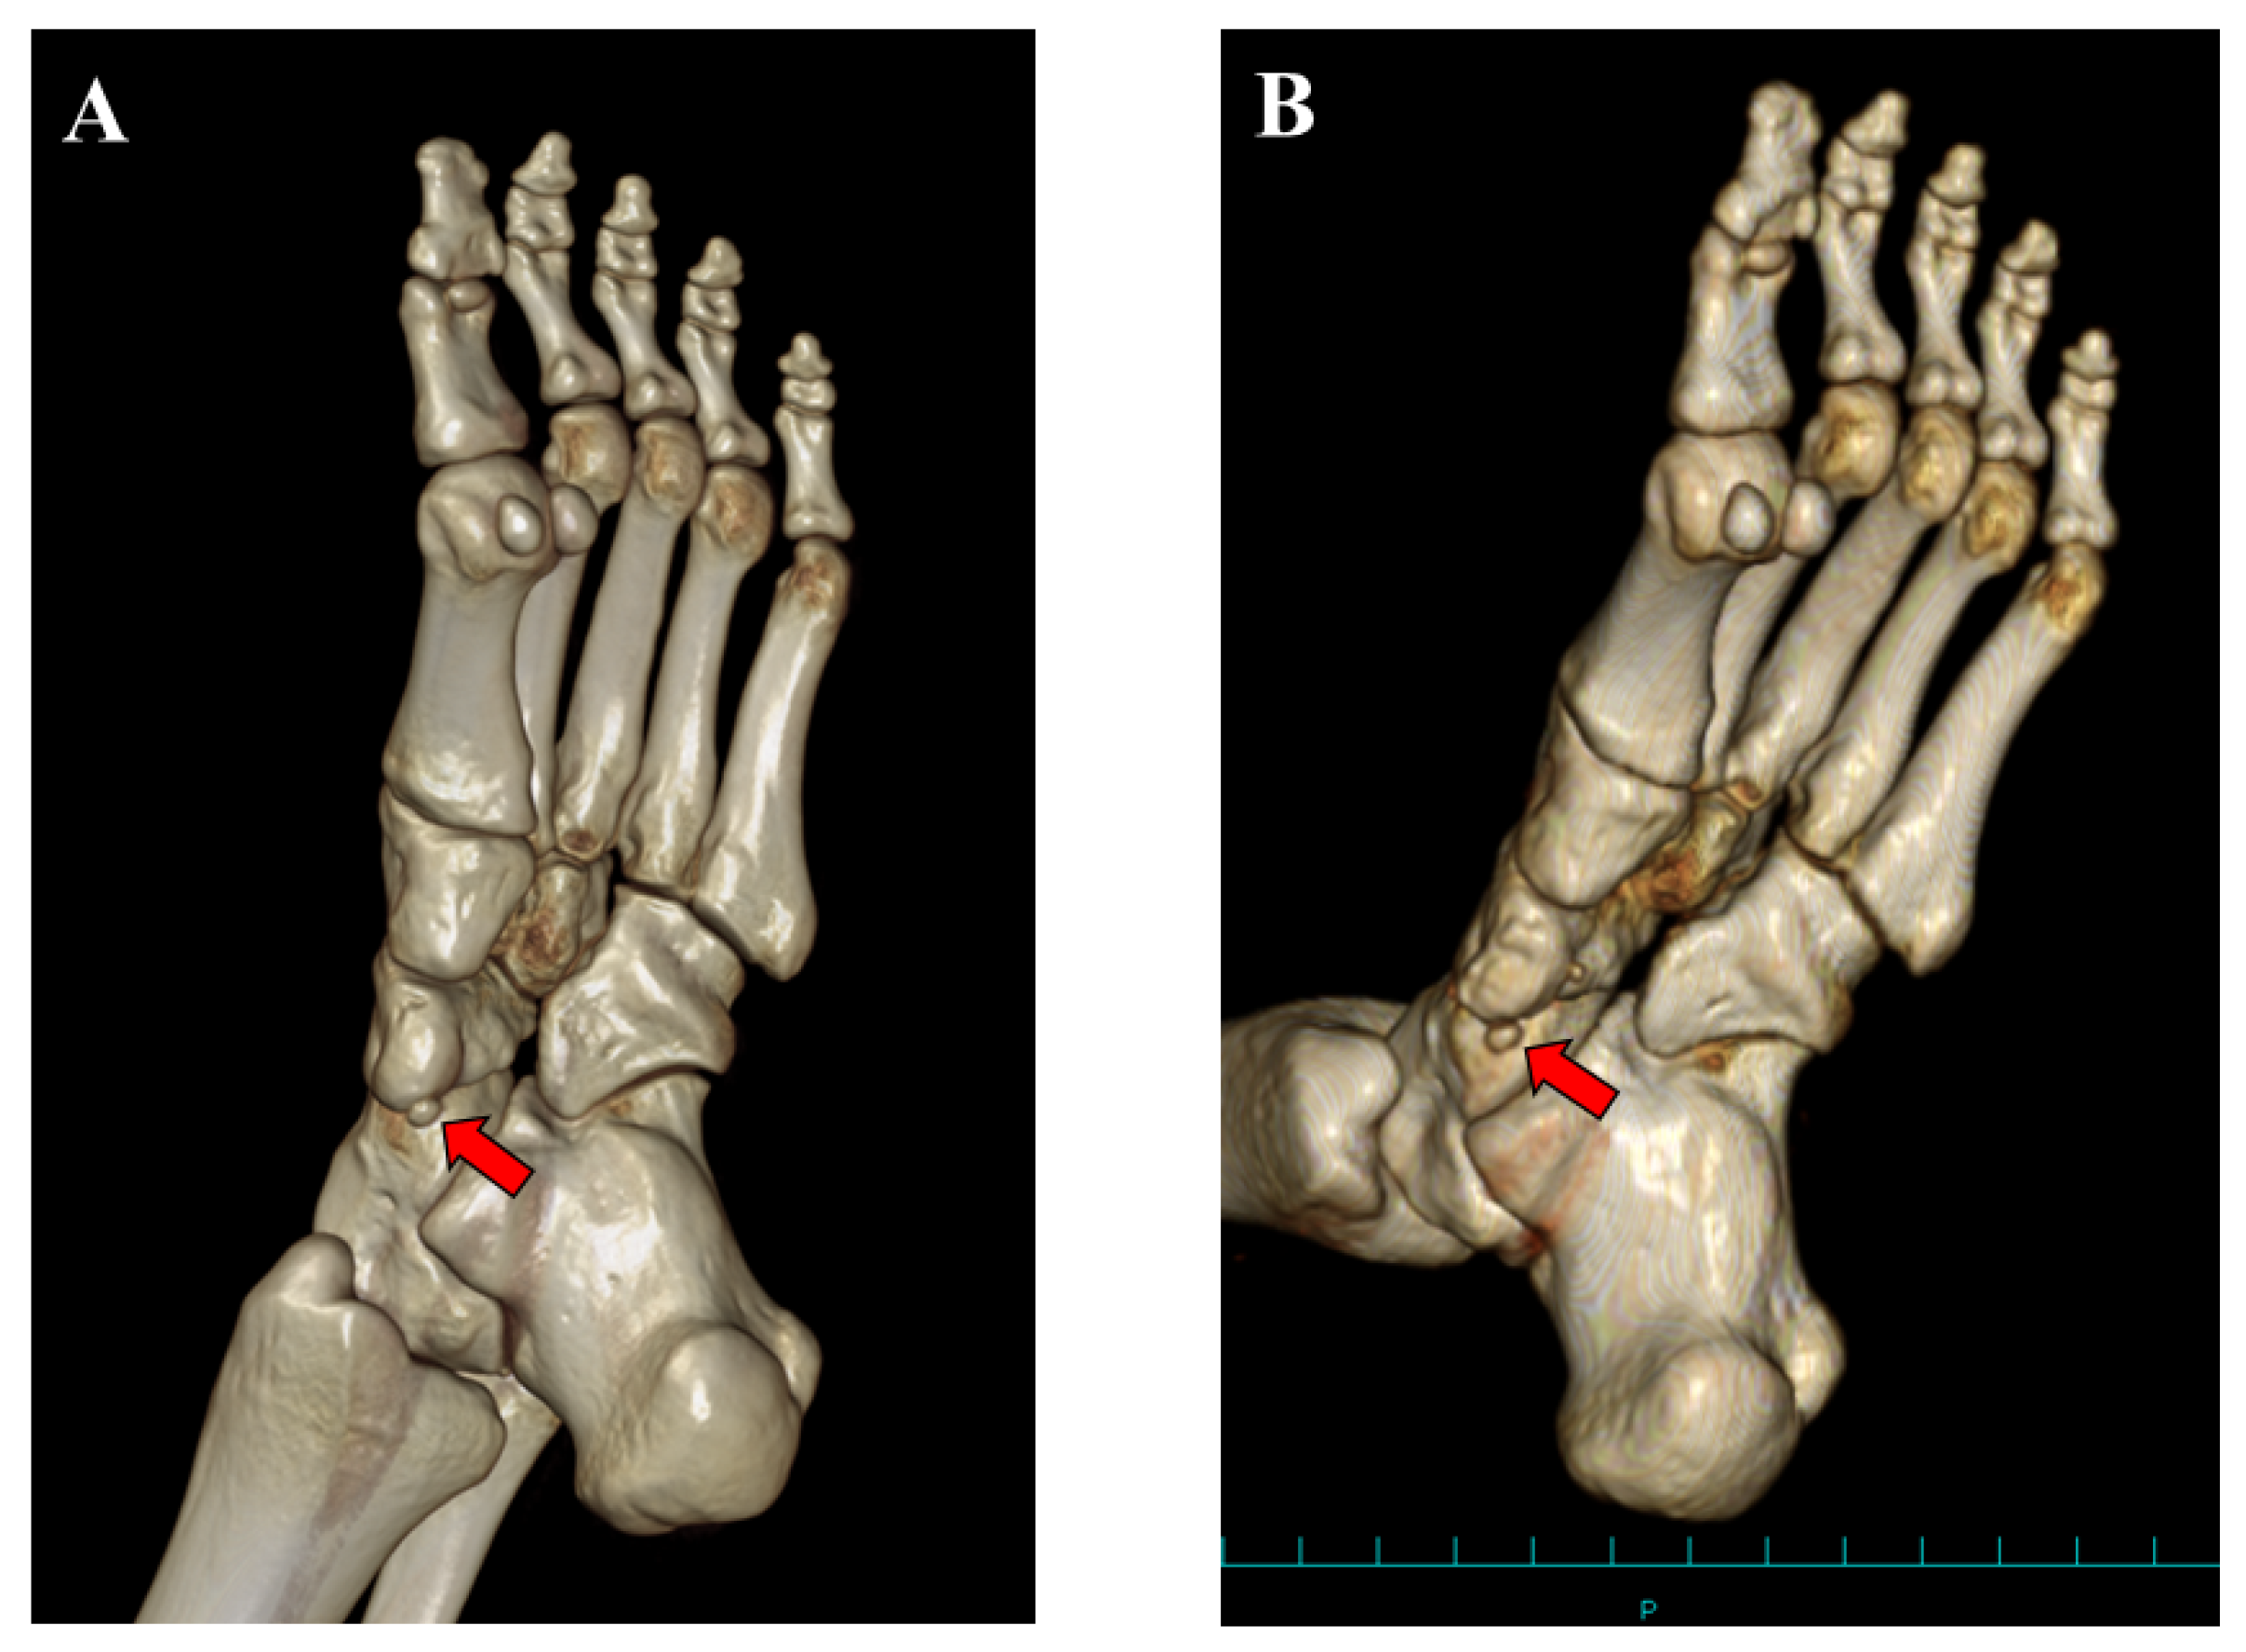

Figure 7.

Three-dimensional computed tomographic (CT) findings: (A) preoperative and (B) postoperative CT findings at 12 months after surgery. A small ossicle (accessory navicular, red arrow) was present postoperatively.

We present a case with symptomatic AN that had been treated conservatively for a prolonged time in accordance with the typical approach for Veitch type 1 AN, in which surgical intervention was subsequently needed to resolve the symptoms. In addition, in this case, the excision of the small ossicle was not needed to resolve the patient’s symptoms although osteotomy of the prominent navicular tuberosity and advancement of the TPT were performed.

The Veitch classification is the system most commonly used to evaluate patients with AN [5,6,7,8]. This classification is easy to understand and broadly used in clinical practice. However, various kinds of morphologies of the AN have been reported [2,10]. Furthermore, Perdikakis et al. first reported a case of multiple ANs [11]. Kalbouneh et al. reported that multiple ossicles were radiographically detected in 1.2% of cases with ANs [10]. The authors also reported that the larger ossicle was united to the navicular while the other round ossicle was clearly separated from the navicular bone, which was similar to the present case. In the present case, the patient had been treated conservatively for Veitch type 1 AN probably because few studies have reported the surgical management of type 1 AN [7]. However, tenderness was present at the united ossicle (navicular tuberosity), not at the separated small ossicle, indicating that the cause of foot pain was derived from the united ossicle. The lesion with high HU on CT images also suggested continued stress loading on the united ossicle. Therefore, from the viewpoint of the pathology, the present case could be classified as Veitch type 3 AN. Clinicians should not simply classify patients with AN into three types using the Veitch classification because this may lead to inappropriate management as presented in the present case.